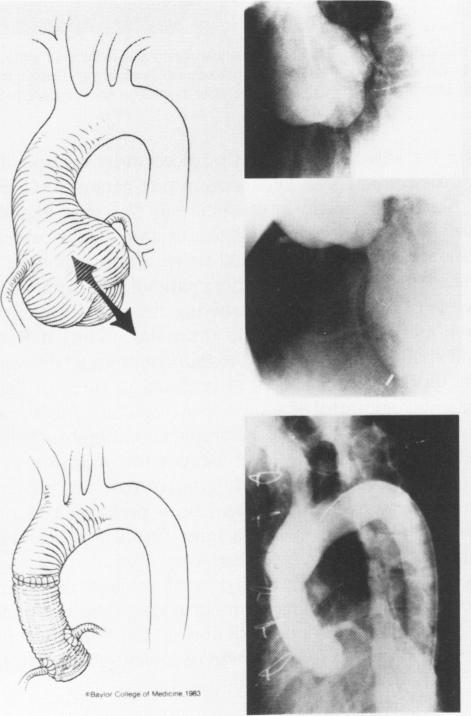

Most patients with Marfan's syndrome have cardiovascular manifestations and complications of these abnormalities lead to death in 50% of patients by the age of 32. This report is concerned with the performance of 79 operations to control these problems in 41 patients during a 16-year period. There were 3 early deaths and 11 late deaths, with survival at 15 years in 62%. The cardiovascular manifestations assumed eight patterns of involvement, in brief, consisting of aneurysms of ascending aorta, mitral valve insufficiency, aortic dissection and dissecting aortic aneurysm, and degenerative distal fusiform aortic aneurysm. These lesions occurred in isolated form or in association with others, hence the larger number of patterns of involvement. Various methods were employed in treatment of aneurysms of the ascending aorta, which was associated with aortic valvular insufficiency in most. The most reliable method of controlling disease at this level was composite valve graft replacement of fusiform aneurysms and separate valve graft operation for dissections occurring in the previously uninvolved aorta. Isolated mitral valve insufficiency was relieved by standard mitral valve replacement and this operation could be safely combined with composite valve graft replacement of the ascending aorta. More distant aneurysms of the aorta, either degenerative or chronic dissections, were susceptible to reconstruction as employed in the nonMarfan patient. Treatment of multiple lesions was staged, treating the more symptomatic condition first. Regular follow-up examination is important in these patients to detect new lesions and to evaluate known lesions. An aggressive approach is suggested in their treatment because 63% of the 11 late deaths in this series were due to lesions that could be successfully treated by presently available methods.

大多数马方综合征患者有心血管表现,这些异常的并发症在32岁时导致50%的患者死亡。本报告关注的是在16年期间对41例患者进行的79次控制这些问题的手术情况。有3例早期死亡和11例晚期死亡,15年生存率为62%。心血管表现呈现出八种受累模式,简而言之,包括升主动脉瘤、二尖瓣关闭不全、主动脉夹层和夹层主动脉瘤,以及退行性远端梭形主动脉瘤。这些病变以孤立形式出现或与其他病变合并出现,因此受累模式较多。治疗升主动脉瘤采用了多种方法,大多数情况下升主动脉瘤与主动脉瓣关闭不全相关。在这个层面控制疾病最可靠的方法是对梭形动脉瘤进行复合瓣膜移植置换,对先前未受累主动脉发生的夹层进行单独的瓣膜移植手术。孤立性二尖瓣关闭不全通过标准二尖瓣置换得以缓解,并且该手术可以安全地与升主动脉复合瓣膜移植置换联合进行。更远端的主动脉瘤,无论是退行性还是慢性夹层,都易于采用非马方综合征患者所采用的重建方法。对多种病变的治疗分阶段进行,先治疗症状更明显的情况。对这些患者进行定期随访检查很重要,以便发现新病变并评估已知病变。建议在其治疗中采取积极的方法,因为本系列中11例晚期死亡中有63%是由于目前可用方法可以成功治疗的病变。